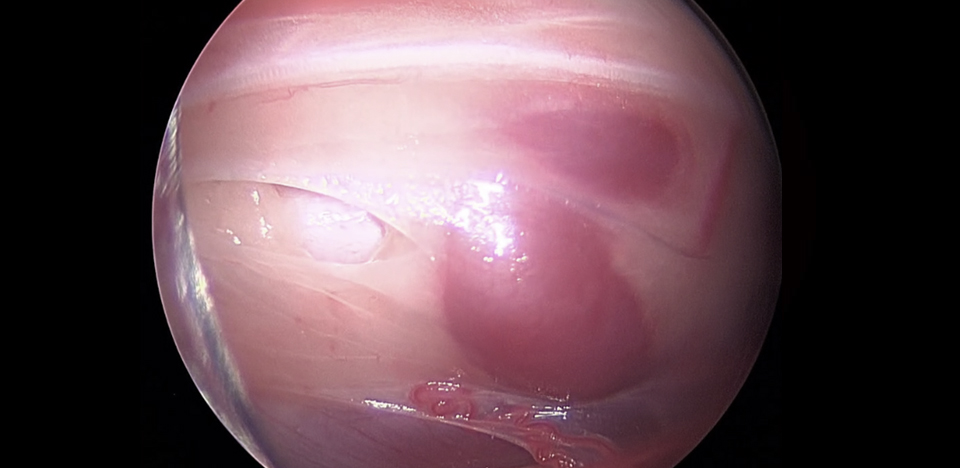

관절 내시경 수술

• 관절 내시경 수술은 관절 내부에 가느다란 카메라를 삽입해 관절면과 연골, 인대 구조를 직접 확인하며 치료하는 방법입니다.

• 작은 절개만으로 관절 내부의 병변을 정확하게 진단하고 불필요한 조직을 제거하거나 수술 치료를 시행할 수 있습니다.

• 관절낭 절개 없이 관절안을 선명하게 관찰할 수 있어 진단 정확도가 높고 수술 후 통증이 현저히 줄어듭니다.

• 슬개골 탈구, 십자인대 손상, 관절 내 신생물 등 다양한 관절 질환에서 빠른 회복과 낮은 합병률을 기대할 수 있습니다.